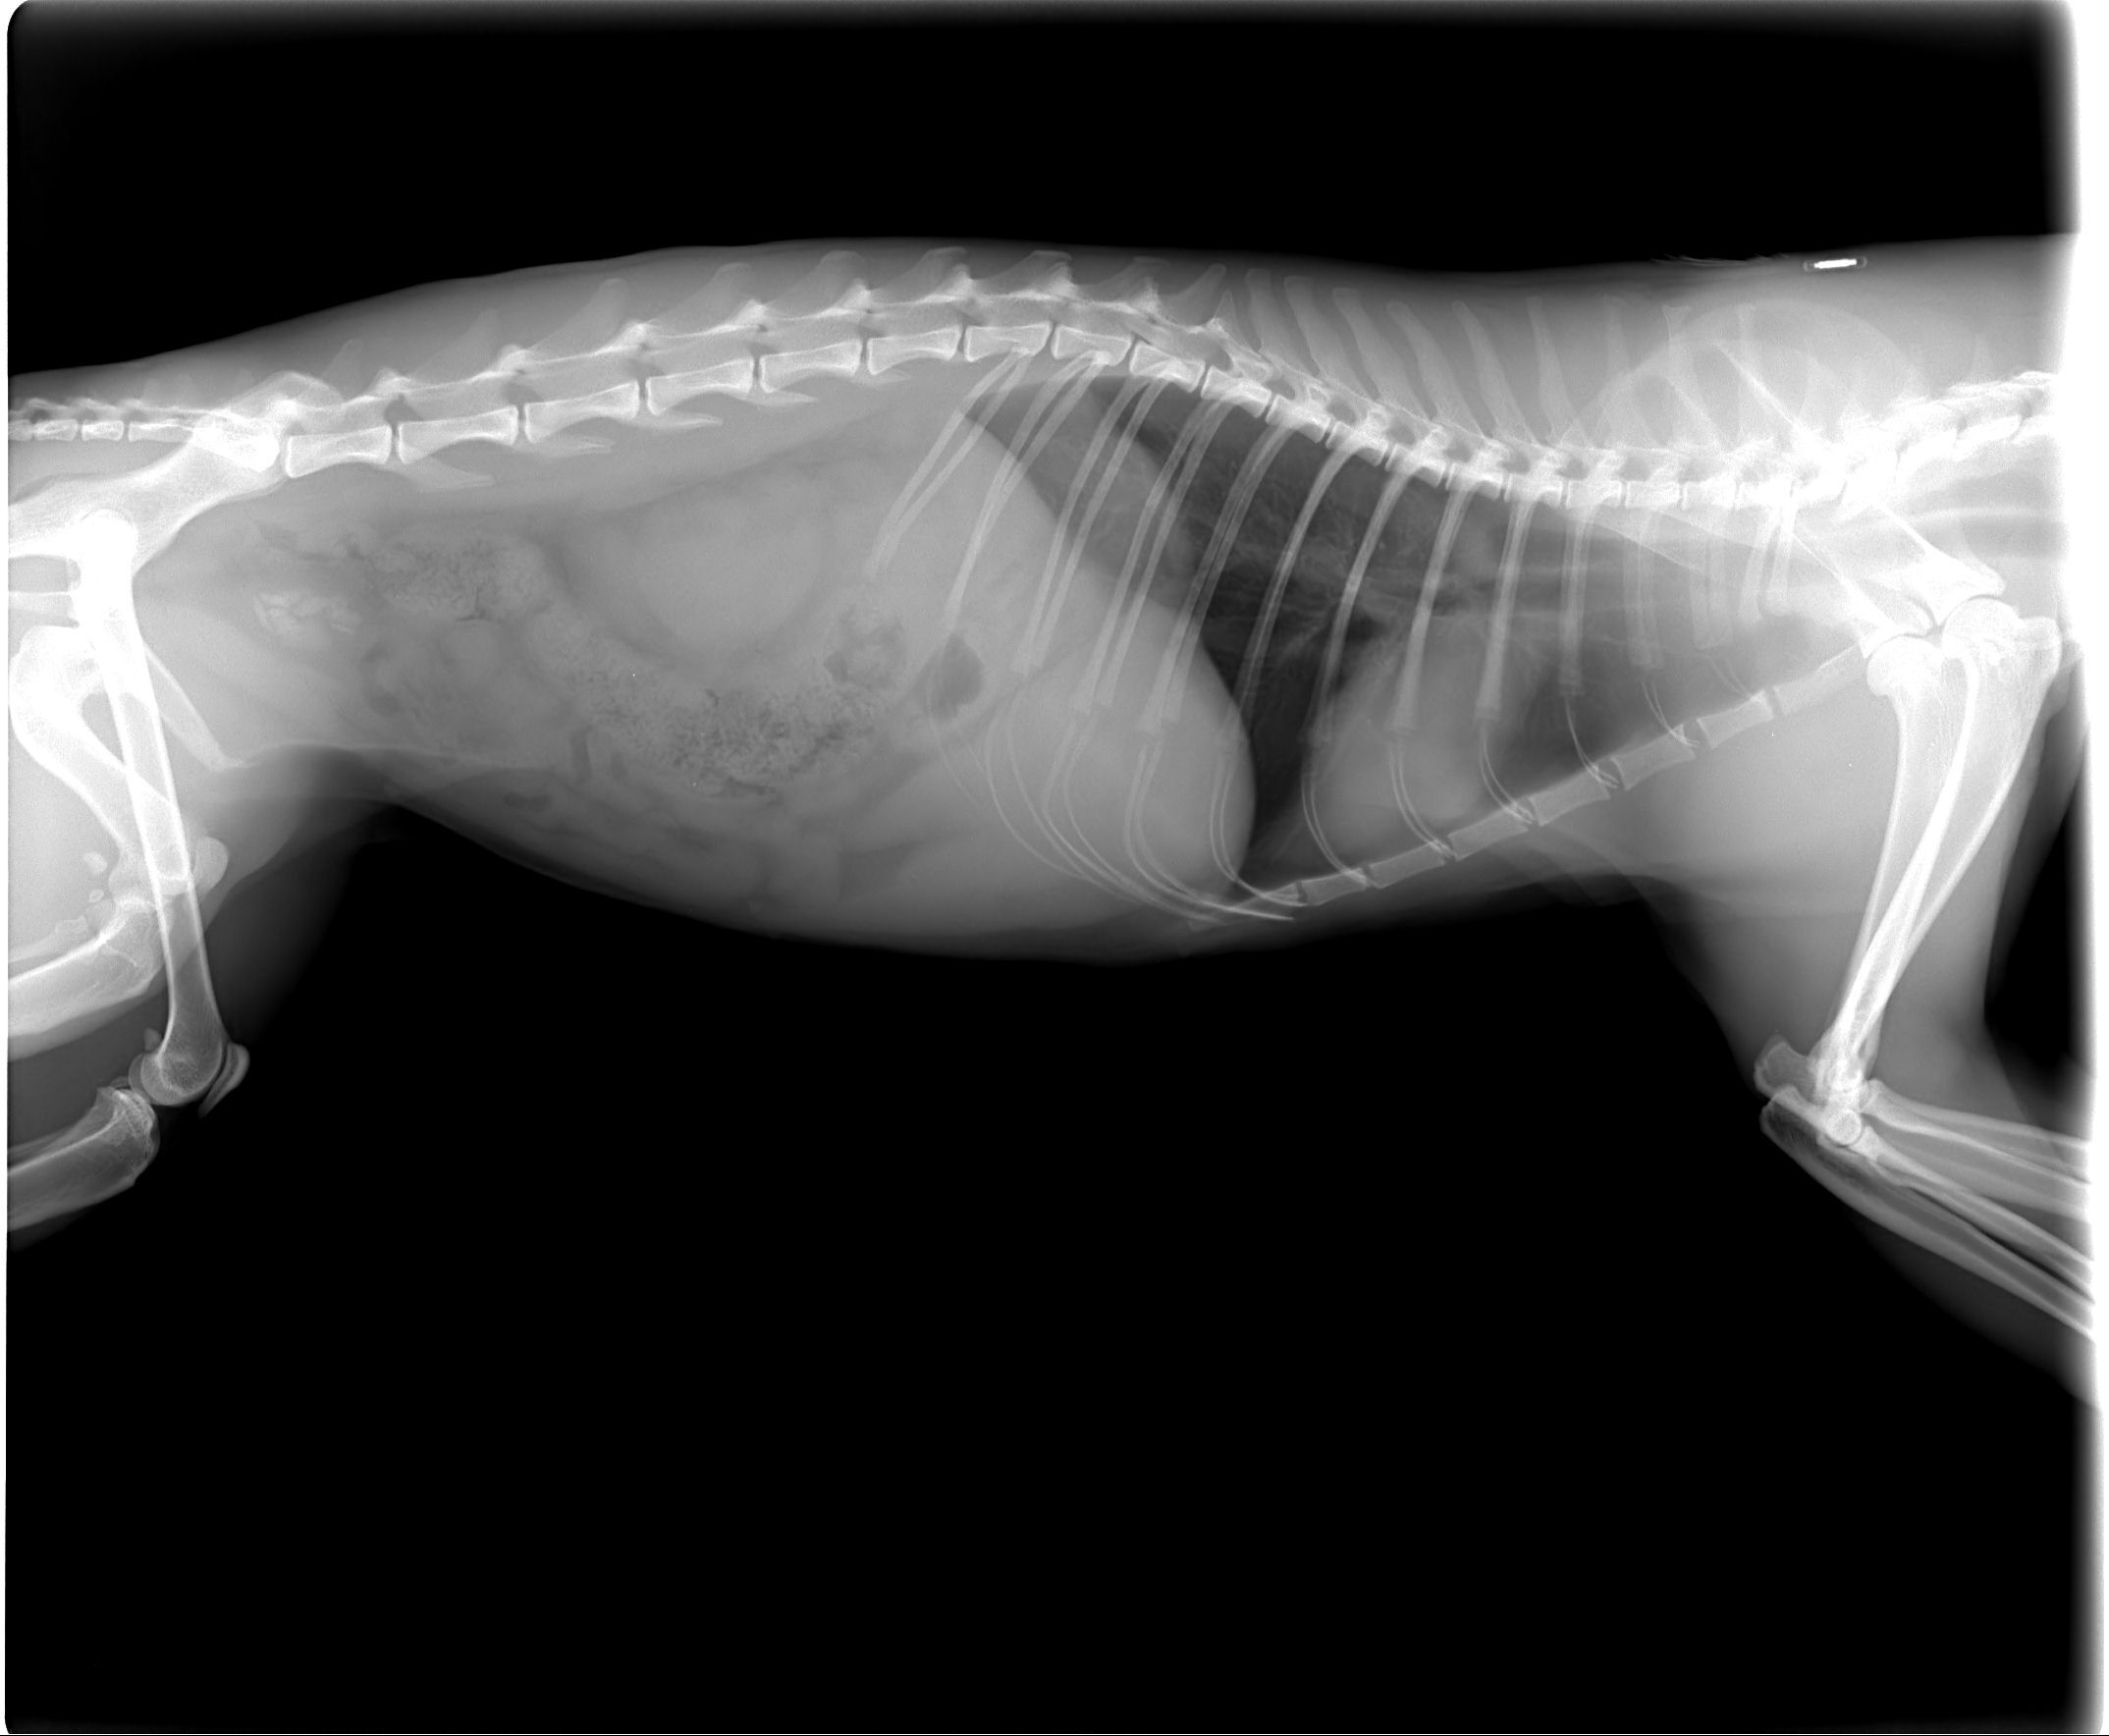

主題: 停車場嚴重血尿虎斑大公貓(好漢) 申請者姓名: 高進隨 花色: 申請日期: 2012-07-21 11:29:52 申請者部落格: 申請者臉書網址: 所在縣市/合作醫院: 台北市/恩加動物醫院 治療費用: 13500元 需求人數: 30人 已結案 (2013-06-27 13:20:09) 報名人員: 小強(已付款)、維琪、王興賢(已付款)、周小蕾(已付款)、王惠珍(已付款)、Tristain Chao(已付款)、靖靖(已付款)、WeiLin Chen(已付款)、冥王星獅子(已付款)、Yun-Ping Lin(已付款)、Ginny Lin(已付款)、Peggy Tsai(已付款)、Debby Hsieh(已付款)、Katilin Chang(已付款)、Jerry(已付款)、縱逸子(已付款)、Ailin Wang(已付款)、婁婁、Jeff(已付款)、維琪(已付款)、CANDY(已付款)、蝸牛(已付款)、Ju-jan Hsu(已付款)、Pinky(已付款)、Sam(已付款)、py(已付款)、Petty Taso、Petty Taso、吳溱溱(已付款)、b_b3003(已付款)、憲忠、小舟(已付款)、小舟(已付款)、小舟(已付款)、春卷(已付款)、 候補人員: 動物病情說明: 這隻虎斑大公貓(名字:好漢)住在台北市家樂福地下停車場中,原本是想要將他進行TNR後,讓他繼續原本快樂的生活!

未料在運送好漢到醫院的途中發現,運送的機車上有一灘不明血跡,仔細查看仍找不出原因,直到好漢住院等待絕育時,才發現他有嚴重血尿,原來運送機車上的血跡是血尿!

在醫生建議之下,先幫好漢進行絕育手術,同時施予針劑治療觀察好漢血尿是否只是單純的發炎所引起。但兩天後好漢血尿依舊,判斷好漢血尿應該是膀胱結石所致。

目前好漢需要進行手術取出膀胱結石以及住院休養,才能恢復健康。希望大家伸出援手,讓好漢免於因結石引發的疼痛和血尿,早日回到停車場中生活!